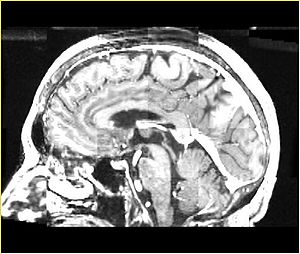

• Checkerboard appearance of unregistered images for the representative data of interest

• Case01